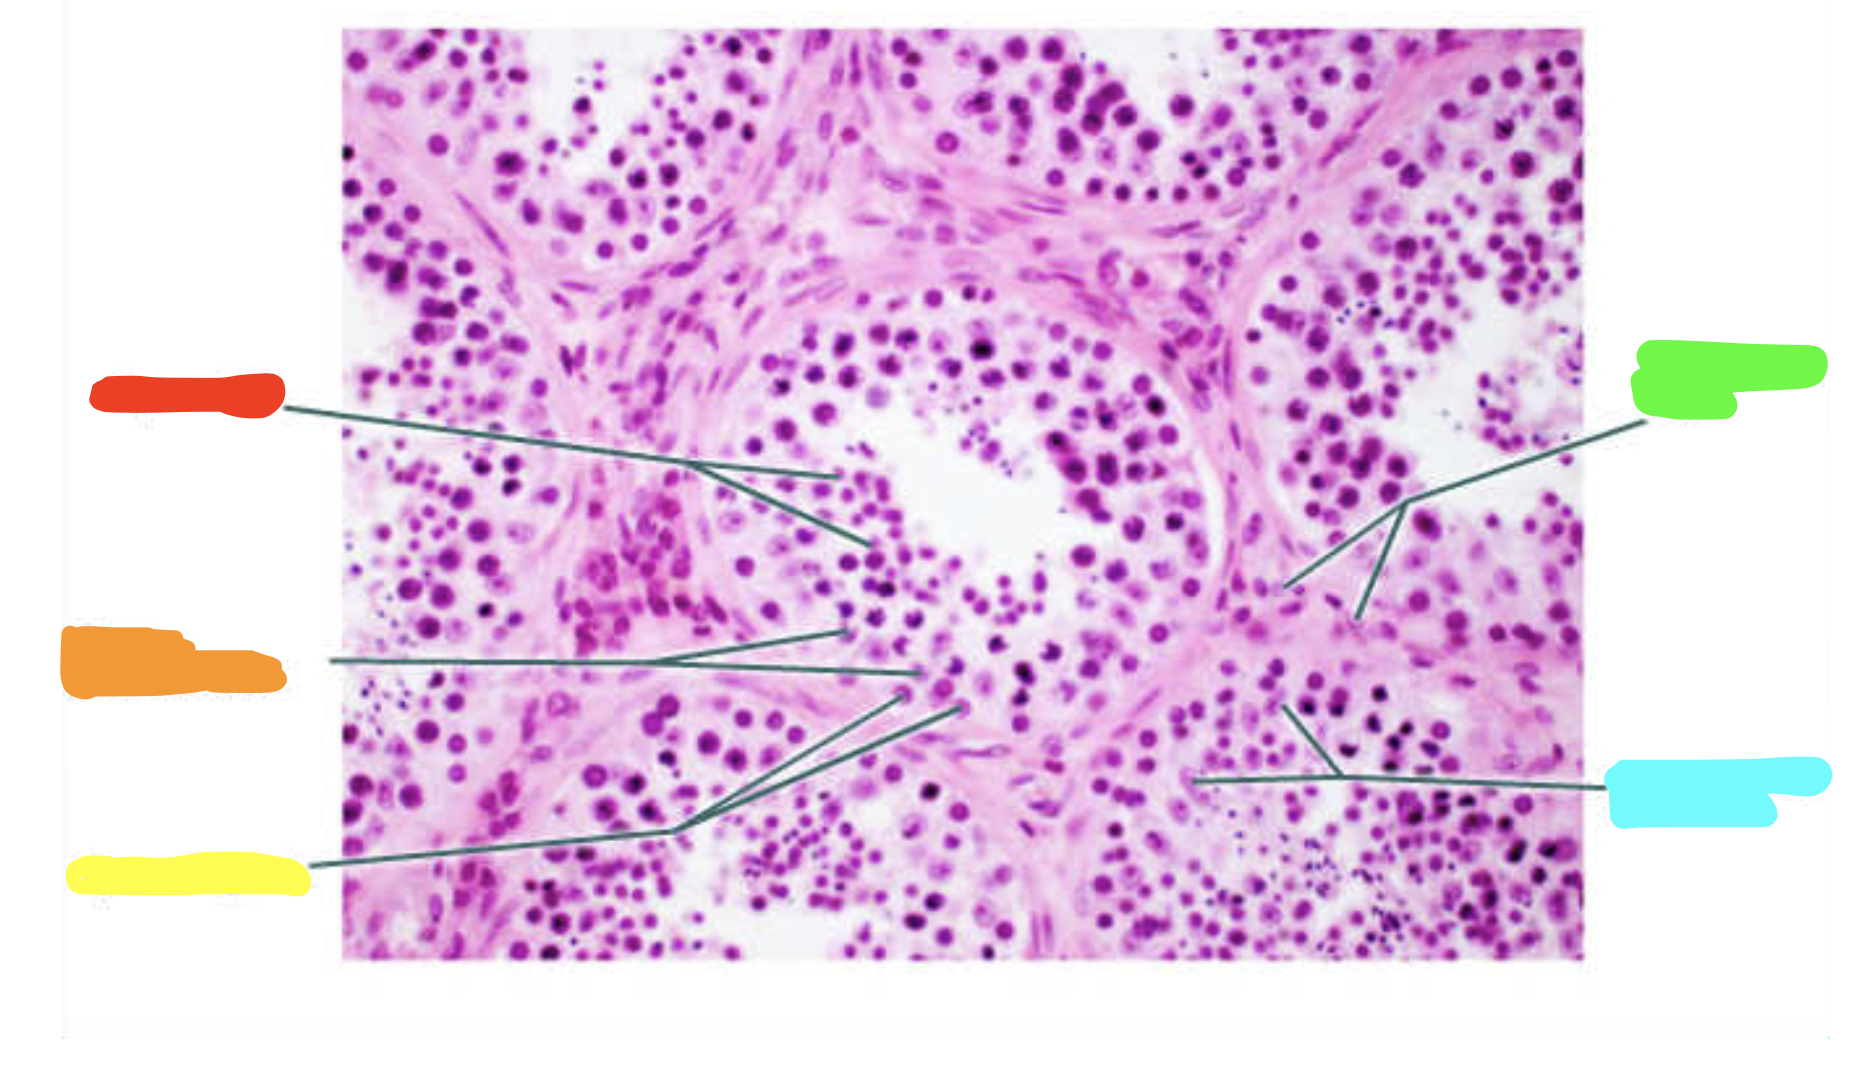

What is this a slide of?

Testis

What is red?

Spermatids

What is orange?

Primary spermatocytes

What is yellow?

Spermatogonia

What is green?

Interstitial cells

What is cyan?

Sustentacular cell nuclei